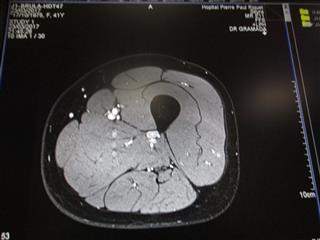

IRM - Imagerie à Résonance Magnétique

image 1 - Estomac à gauche et Foie Rate Pancréas à droite - Oesophage au milieu.

image 2 - Coupe de la Cuisse - Fémur en noir au milieu, Muscle en blanc et graisse en noir avant la délimitation de la peau

image 1                                                        image 2

Spéciale Dédicace à Marie-Claude, notre Docteur qui nous a accompagnée et a fait ces 3 clichés.